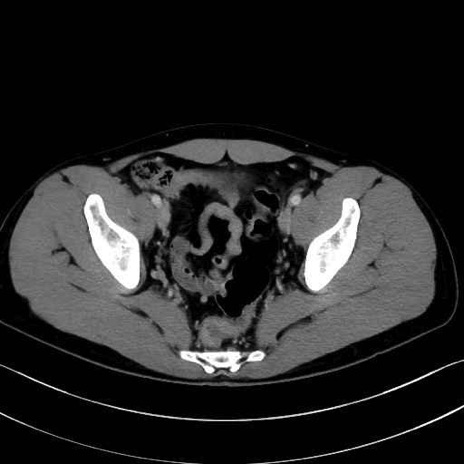

1. 体幹部(腹部・背部・後腹壁)の筋肉

腹直筋 (Rectus abdominis)

外腹斜筋 (External oblique)

内腹斜筋 (Internal oblique)

腹横筋 (Transversus abdominis)

腰方形筋 (Quadratus lumborum)

広背筋 (Latissimus dorsi)

脊柱起立筋 (Erector spinae)

多裂筋 (Multifidus)